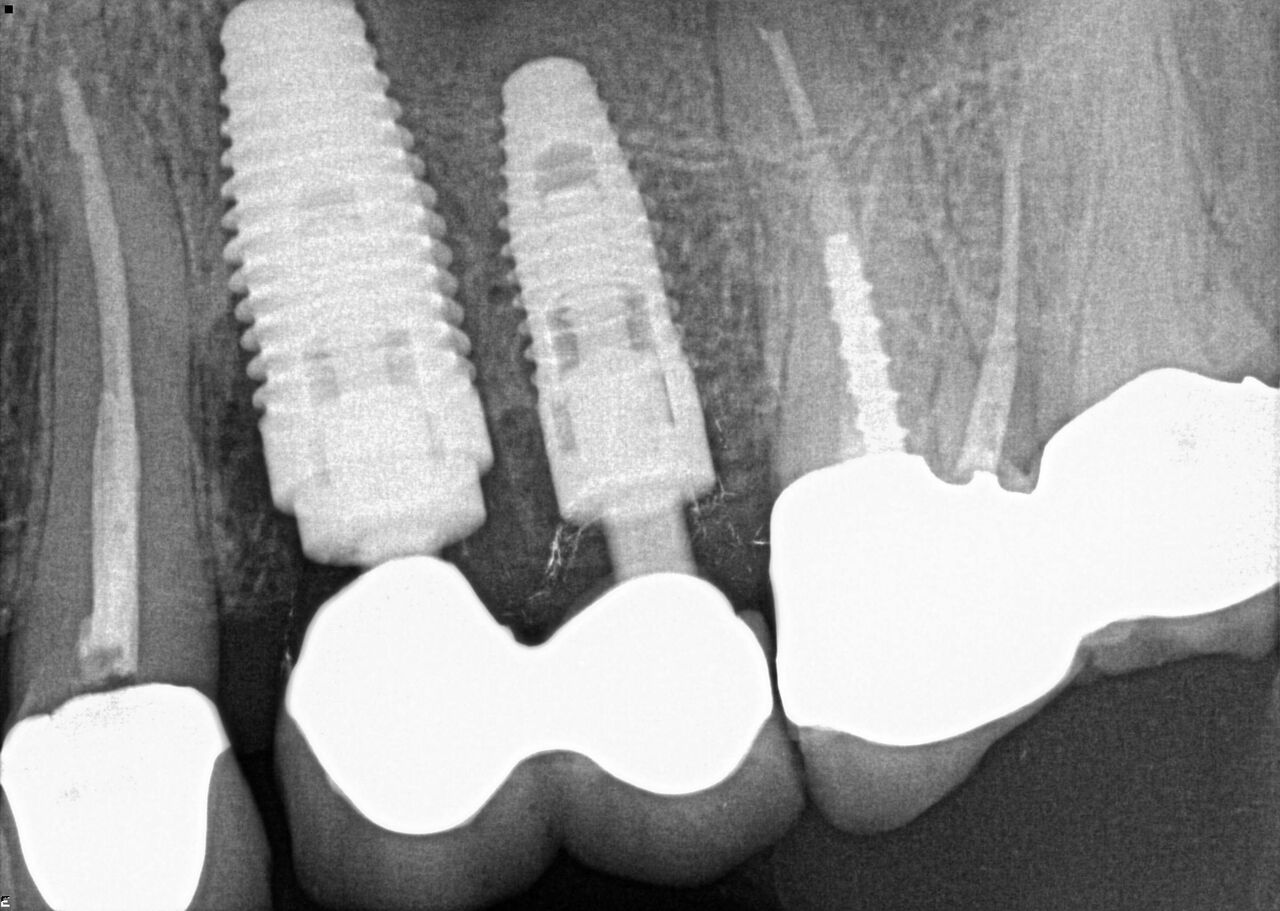

(17.) Case 3 initial radiograph of bridge on Nos. 6 through 9 and crown on No. 10.

Figure 17

(18.) Case 3 initial radiograph of bridge on Nos. 6 through 9 and crown on No. 10.

Figure 18

(19.) Initial clinical evaluation of Nos. 6 through 9 bridge and crown on No. 10.

Figure 19

(20.) 6-month integration confirmation of Nos. 6 through 10.

Figure 20

(21.) 6-month integration confirmation of Nos. 6 through 10.

Figure 21

A 42-year-old man presented with a very loose bridge on Nos. 6 through 9 with periodontally compromised retainers on Nos. 6 and 9 (Figure 17 through Figure 19), and endodontically involved No. 10 with a calcified canal. Teeth Nos. 6, 9, and 10 were extracted, the sockets fully debrided, and pontic soft tissue on Nos. 7 and 8 sculpted to be symmetrical in soft tissue contour with the contralateral lateral incisor and central incisor locations. Implants were secured in position Nos. 6 through 10 (Figure 20) in excess of 45 Ncm, the bone was milled to provide unimpeded seating of temporary abutments, and temporary crowns were fabricated chairside and adjusted to be out of occlusion in centric relation and all excursions. The temporary crowns were cemented after extrusion of excess cement extraorally and the patient was prescribed antibiotics, analgesics, and instructed in postoperative care particular to immediately provisionally restored implants. At 6 months, integration was confirmed (Figure 20 through Figure 23) and after placement of scanning abutments, the implants and soft tissues were scanned. Final crowns were fabricated from the scanned images and were cemented after extrusion of excess cement extraorally (Figure 24 through Figure 26), and oral hygiene procedures were reviewed.